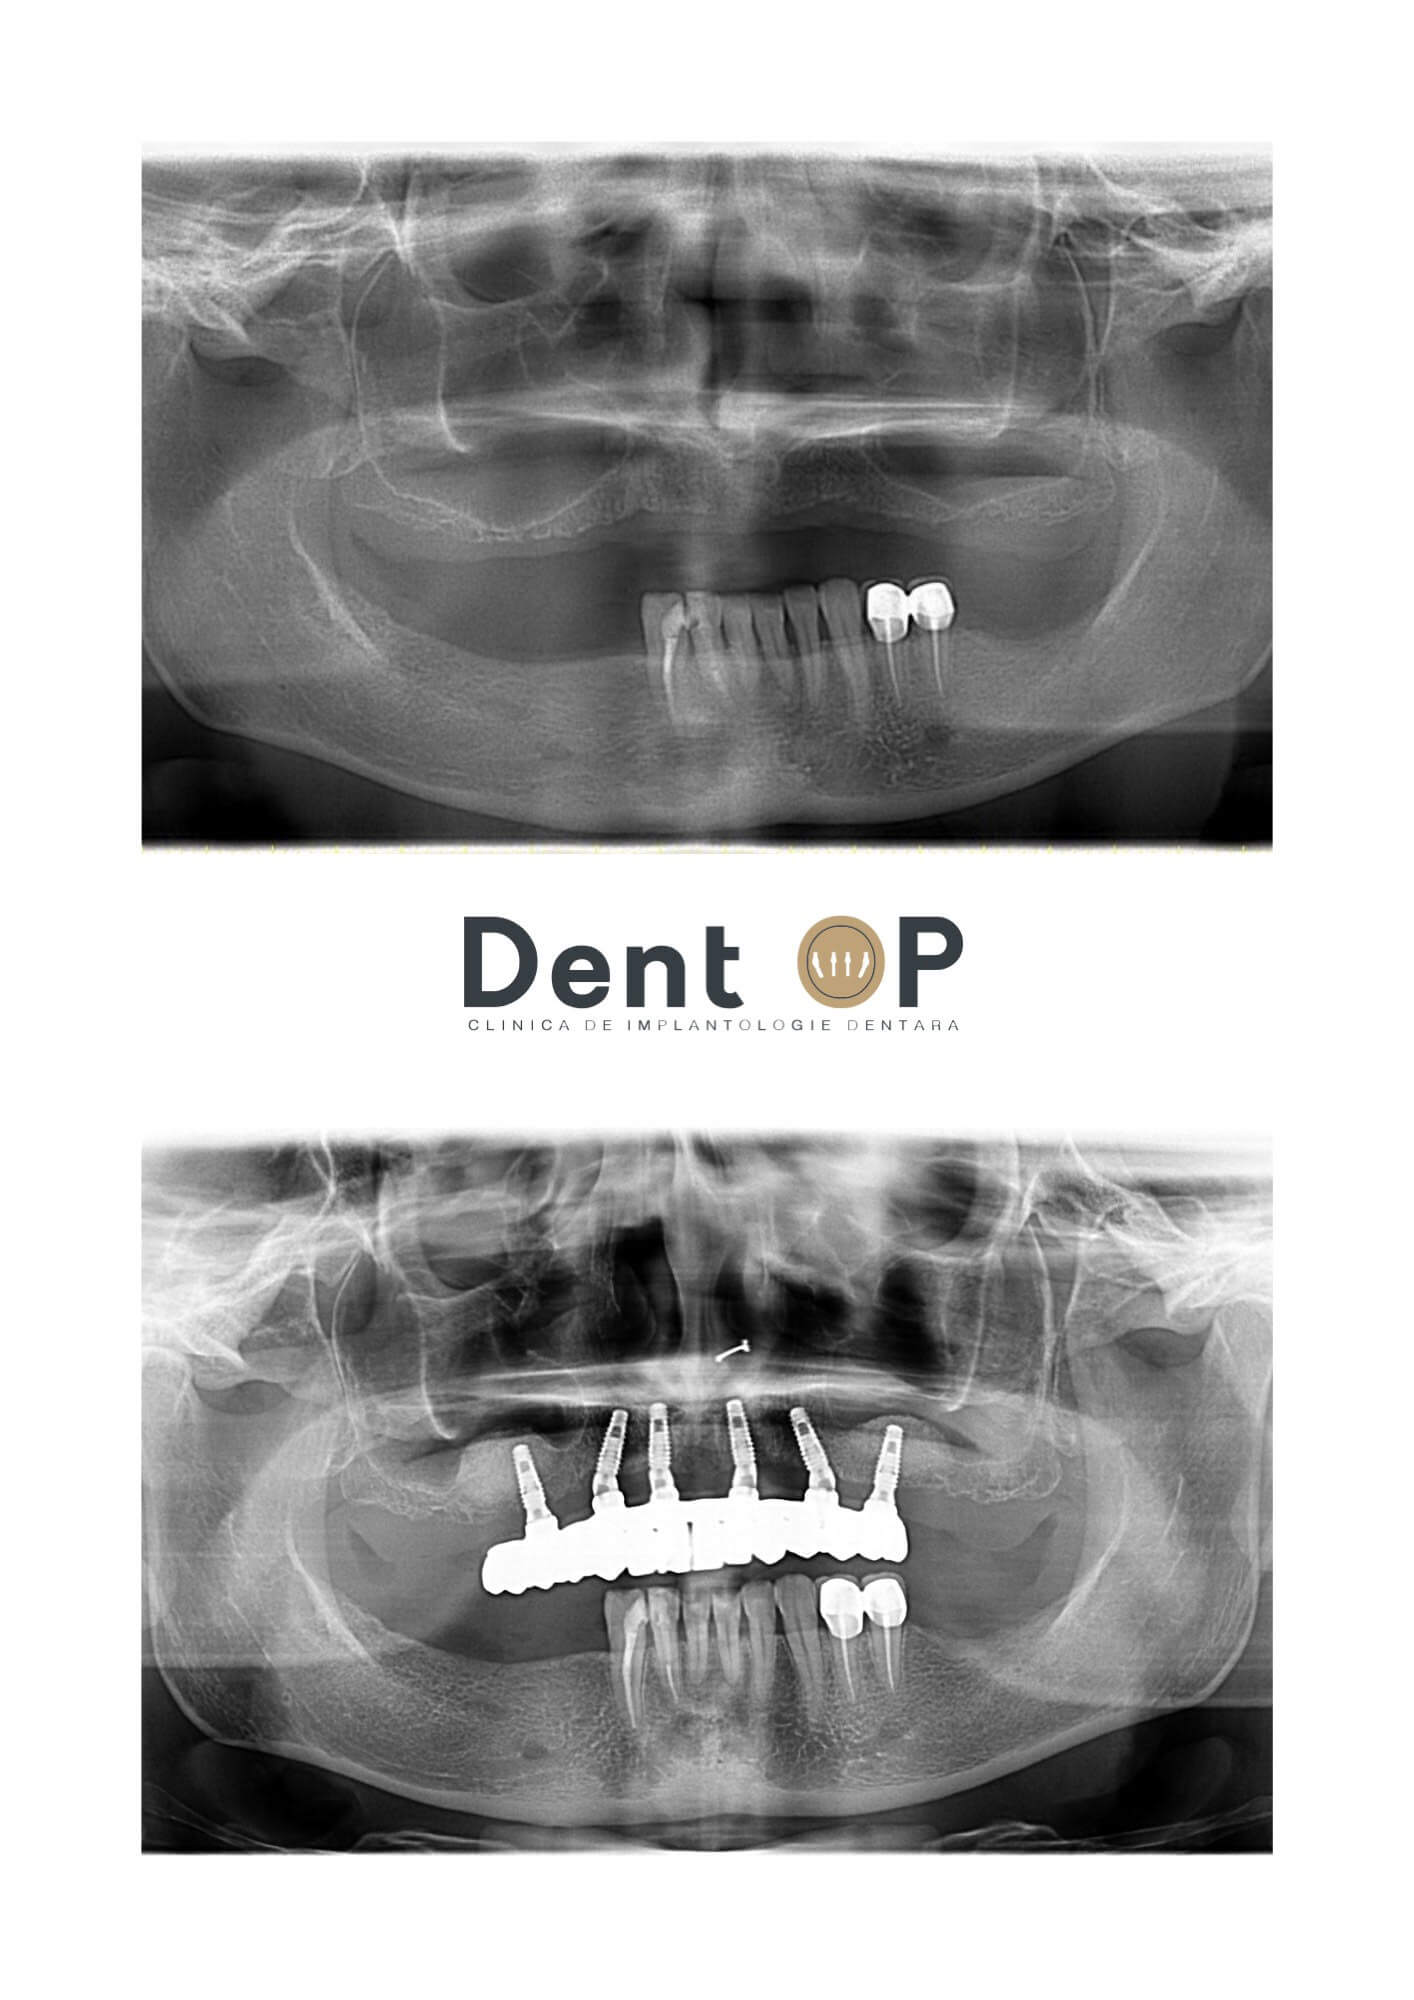

Am atașat mai jos radiografia doamnei S. înainte și după inserarea implanturilor dentare:

Doamna S. a beneficiat de 6 implanturi dentare la maxilar într-o singură ședință sub Sedare Conștientă. Întrebată cum i s-a părut intervenția, doamna S. a răspuns: ,,Nu-mi amintesc prea multe din cadrul intervenției. Parcă auzeam la un moment dat sunetele aparaturii medicale.”